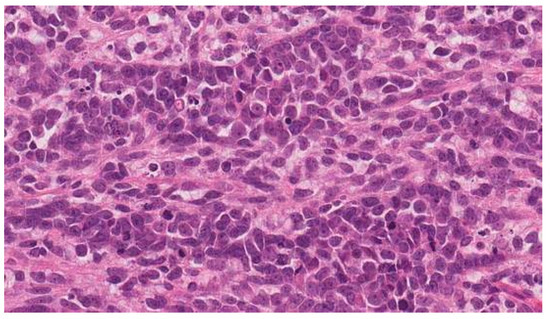

2. Case Report